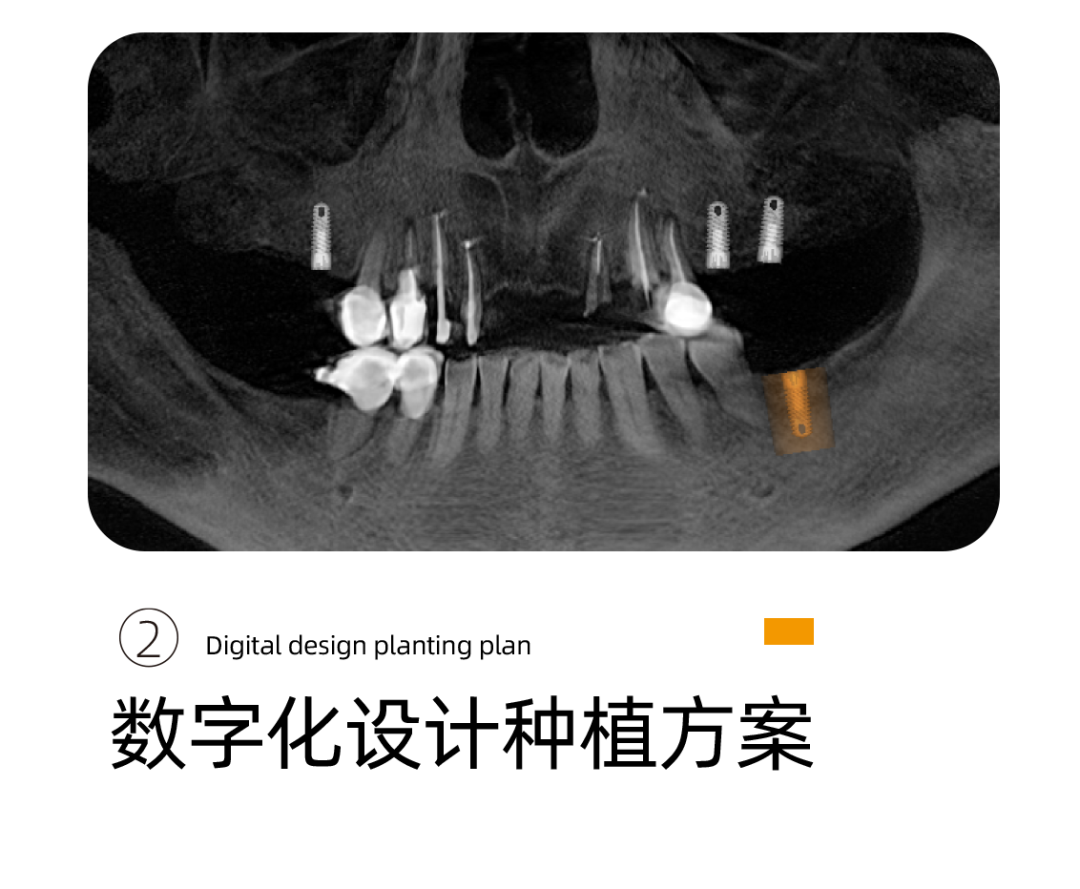

这是阿姨来找李雪松院长看牙最开始的样子。

不是这样的图片,我们都没有办法理解这样的口腔情况对一个老人来说意味着什么。阿姨说的吃东西靠吞不是被夸大的感受,而是她每天的日常。

针对阿姨的情况,李雪松院长为阿姨指定全套的数字化种植方案。

什么是UNIC数字化种植方案呢?

其实就是借助Sirona CBCT全景影像信息和相关修复信息为基础,借助数字化专业种植设计软件进行术前诊断和种植方案规划。